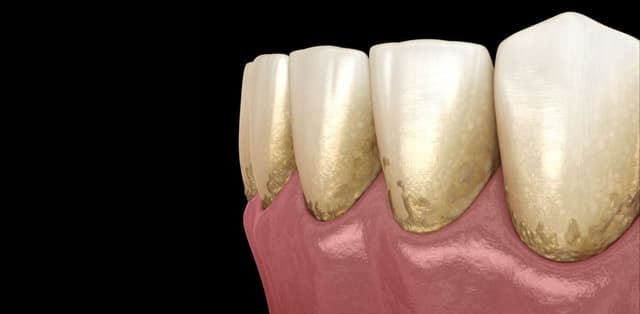

Cao răng là tổ hợp cặn lắng cứng của các muối vô cơ (bao gồm canxi carbonat và phosphate) kết hợp với các cặn lắng mềm (bao gồm mảnh vụn thức ăn, các khoáng chất trong khoang miệng), vi khuẩn, tế bào chết biểu mô, cặn lắng sắt trong huyết thanh. Vị trí bám của […]

Cao răng bám chặt trên răng lâu ngày nếu không được xử lý sẽ dẫn tới những hậu quả vô cùng nguy hiểm đối với sức khỏe răng miệng. Vậy cao răng hình thành như thế nào, làm sao để loại bỏ cao răng? Bài viết sau đây sẽ giải đáp cho bạn những thắc […]